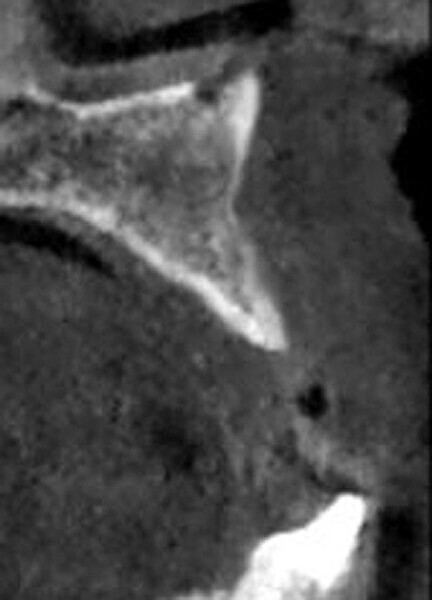

Fig. 2: CBCT cross-section demonstrating insufficient ridge width facial-palatally to permit implant placement in the healed extraction sites.